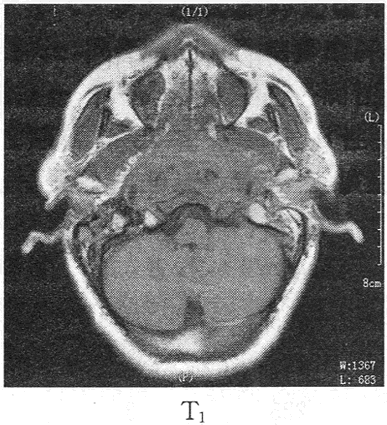

患者男,64岁,反复鼻出血3个月,伴头痛耳鸣1个月余,患者行MR图像如下,最有可能的诊断是